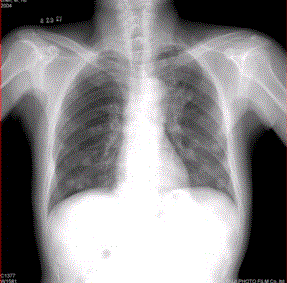

问题 患者男,45岁,因肝硬化、肝癌行肝移植术后6个月,咳嗽2周,来院复查。CR及CT影像如下图。 该例最可能的转移途径为

选项 A.经肺动脉 B.经肺动脉至淋巴管而后到肺外围 C.经纵隔淋巴结逆流到肺门淋巴结,再经肺内淋巴管到肺外周 D.经胸膜腔 E.经气道 F.经支气管动脉

答案 A

解析 A